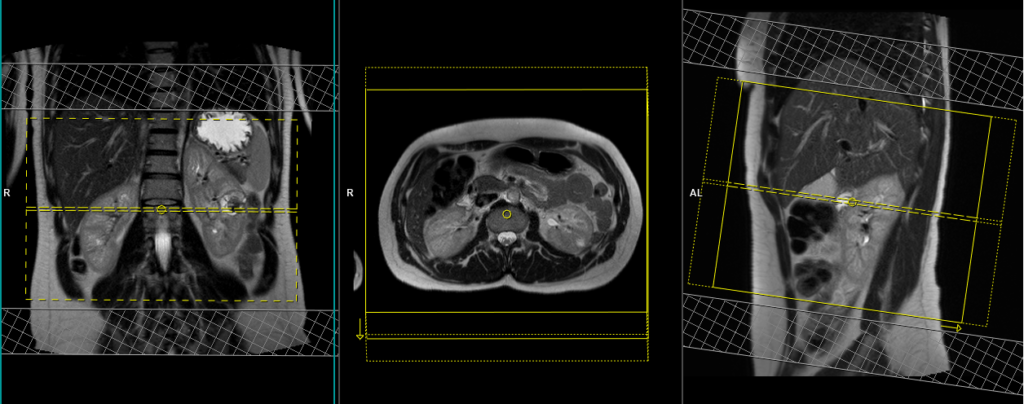

T2 tse\haste fat sat breath hold 4mm axial

Plan the coronal slices on the axial plane and angle the positioning block parallel to the right and left kidneys. Check the positioning block in the other two planes. Ensure an appropriate angle is given in the sagittal plane (parallel to the long axis of the kidney). The slices should adequately cover both kidneys from the anterior to posterior direction. Phase oversampling should be used to prevent wrap-around artifacts. Consider adding saturation bands at the top and bottom of the block to minimize artifacts caused by fat signal, arterial pulsation, and breathing. Instruct the patient to hold their breath during image acquisition.

Parameters HASTE FAT SAT

TR 2000-2500 | TE 90-110 | FAT SAT SPAIR | NEX 1 | SLICE 4MM | MATRIX 320×256 | FOV 300 | PHASE R>L | OVERSAMPLE 50% | TRIGGER NO |

Parameters T2 FAT SAT

TR 6000-7000 | TE 150 | FAT SAT SPAIR | NEX 1 | SLICE 4MM | MATRIX 256×208 | FOV 280-300 | PHASE A>P | OVERSAMPLE 80% | IPAT ON |